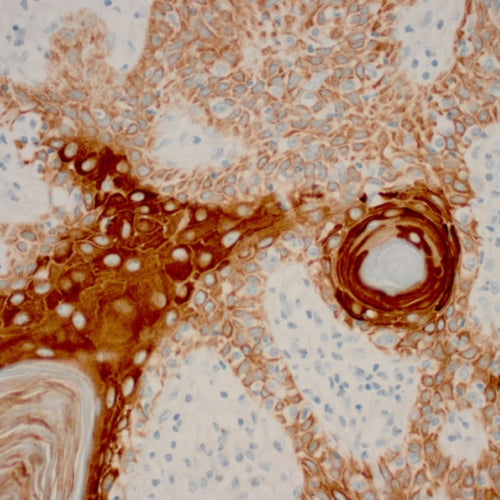

In the 1960’s and 1970’s a novel method was developed which helped pathologists to diagnose cancer cells. The method was based on using antibodies to specifically bind to protein antigens within the cells and tissue elements of a tissue section on a microscope slide. This was followed by using a “detection chemistry” to visualize the binding, such that it could be seen using a light microscope. The method is called immunohistochemistry, or “IHC” for short.

Since that time many thousands of antibodies have been developed for use in IHC. Each one will specifically bind with only one protein site. Through experimentation and research, pathologists now have a large menu of different proteins which can be detected and visualized within the specimens on the microscope slides. The presence or absence of these proteins provides information from which to form a diagnosis.

In histology, we can use pure antibody preparations to specifically bind to protein antigens in tissue sections. Since antibodies themselves are too small to be seen under a microscope, we can “label” them with colored tags which can be observed under the microscope. The proteins can be localized within cells, outside of cells, or even within cell nuclei.